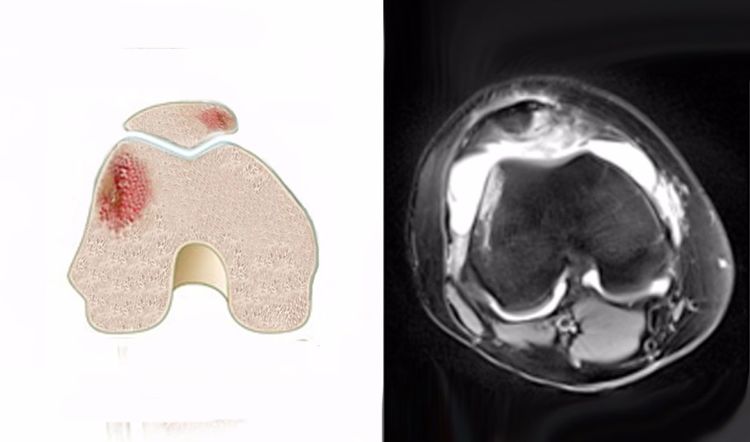

骨挫傷の1例、膝の骨挫傷です。 黒(灰色)っぽいのが骨です。 黒い骨を横切るように入っている白いイガイガの線が骨挫傷の部分です。 mriでは膝(脛骨)の横径の半分ほど亀裂が入っていますが、これでもレントゲンでは写ってきません。 今回は手術は人工関節 手術は先ず膝関節内の壊れた骨、砕けて辺りに飛び散った骨の破片を取り除き、人工関節を入れる手術です。 手術そのものの難易度はそれ程高くないのですが、むしろ怖いのは感染症です。 万一どこかに感染すれば人工関節は摘出せねば 骨挫傷とは? 骨挫傷とは、大きな外力によって骨内部の組織が損傷している状態です。 骨挫傷は、骨折と違い骨の連続性は保たれています。 そのため、簡単にいうと 骨折まで至っていない骨のケガを骨挫傷 という認識でいいと思います。 骨挫傷の場合は、レントゲンでは異常がわかることが良くないです。 そのため、MRI検査を行うと異常がわかり骨挫傷と診断されることが多いよう

3531両踵の骨挫傷の事で 更新 3月の始めにMRIで検査した結果、両踵の骨挫傷と診断されました。 左は重症で骨折と同じ状態といわれ、左だけ数週間、固定しました。 2週間後、レントゲンで経過を観察すると、だいぶマシになってるのでリハビリをVol13 骨挫傷 診断 レントゲンでは所見が見られなくても、mriで骨髄(骨の内部)に生じる異常信号像を骨挫傷と言います。mriのt1像で低信号(黒く)、stir像で高信号(白く)を呈しまず。 骨挫傷って? 骨挫傷とは骨が損傷した状態です。 膝関節や足首のケガに多く見られます。 骨のケガというと骨折を思い浮かべると思いますが骨挫傷は折れてはいません。 骨の表面もしくは内部に微細なキズができ炎症を起こした状態になります。 骨挫傷はレントゲンでは判断できず、確定診断にはMRIをとる必要があります。 そのため、ただの打撲と診断されることもありますが3週間

私たちの膝の骨の表面は、衝撃を吸収するクッションのような軟骨組織に覆われており、 大腿骨 (だいたいこつ) と 脛骨 (けいこつ) をつなぐ 膝関節 (しつかんせつ) は、軟骨があることによってスムーズな動きを維持しています。 この軟骨組織に、スポーツや外傷、事故、加齢などによって8/5/17 変形性膝関節症 による 骨挫傷 と診断されました。 骨挫傷を起こしている部位のレントゲンを見返してみても、レントゲンでは所見は認めませんね。 医師 症例 70歳代 女性 左膝痛 こちらの症例でもレントゲンでは、変形性膝関節症を疑う所見を認めていますが、骨折ははっきりしません。 ところが、MRIをみてみるとSTIRでは、大腿骨及び脛骨の近位に 著明な骨髄浮腫 を疑う高信号を認